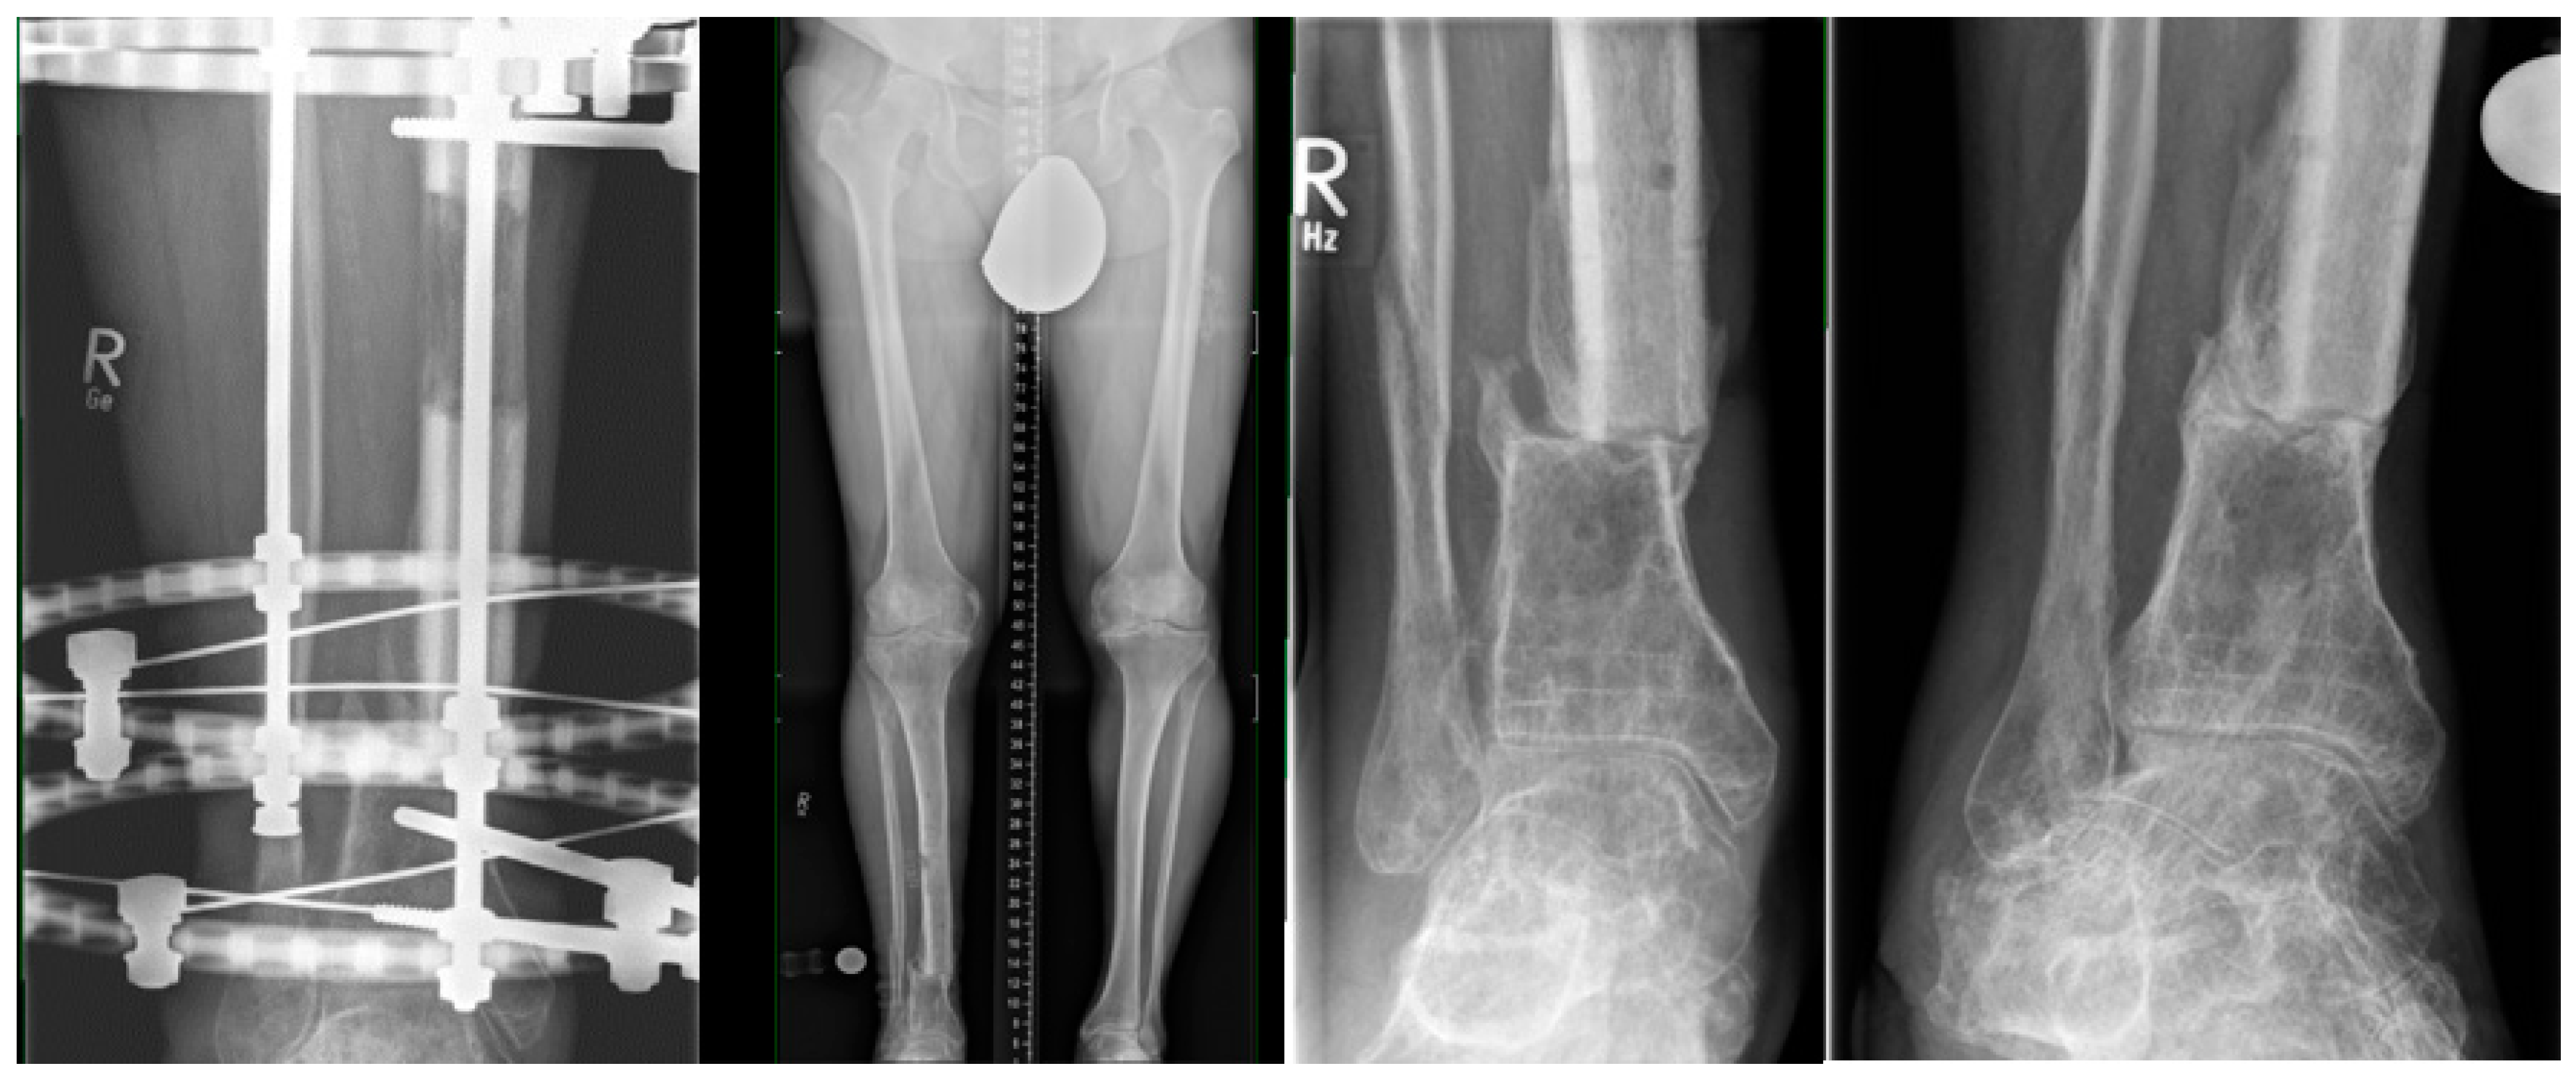

2.2. All-Internal Segmental Bone Transport with Motorized Nails

2.3. Bone Segment Transport Nails (STN)

2.4. Plate-Assisted Bone Segment Transport (PABST)